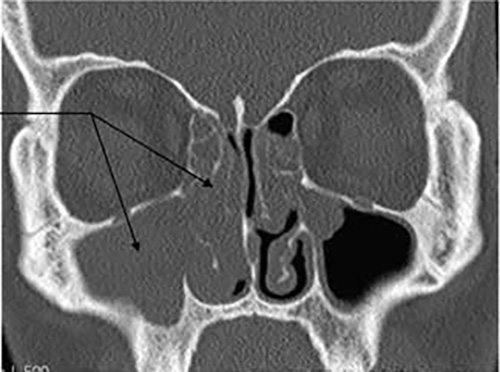

Deviated septum, polyps, turbinate hypertrophy — Professor Veer explains the diagnostic approach and the full range from medical management to septoplasty.

Chronic sinusitis can be dramatically improved — Professor Veer reviews the evidence for each treatment and explains when FESS surgery is the best option.